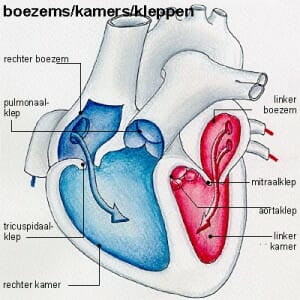

Bij een hartaanval raakt een bloedvat van het hart ineens afgesloten. De kransslagader van het hart is verstopt, waardoor er geen bloed meer naar een deel van de hartspier kan stromen. Hierdoor krijgt je hart te weinig zuurstof. Het gevolg is dat een deel van de hartspier beschadigd raakt en afsterft.

Een hartinfarct ontstaat meestal omdat een kransslagader is dichtgeslibd. Er liggen drie kransslagaders om het hart heen. Deze aders zorgen voor de continue bloedtoevoer naar het hart. Een kransslagader raakt meestal verstopt door een bloedstolsel (arteriële trombose). Als gevolg van aderverkalking kan het bloed niet meer goed stromen, waardoor de kransslagader verstopt raakt.

Heel soms zijn de drie slagaders gezond, maar wordt een hartaanval door ‘spasmen’ veroorzaakt. Deze ‘spasmen’ kunnen ontstaan door hevige stress of door het gebruik van bepaalde medicijnen.